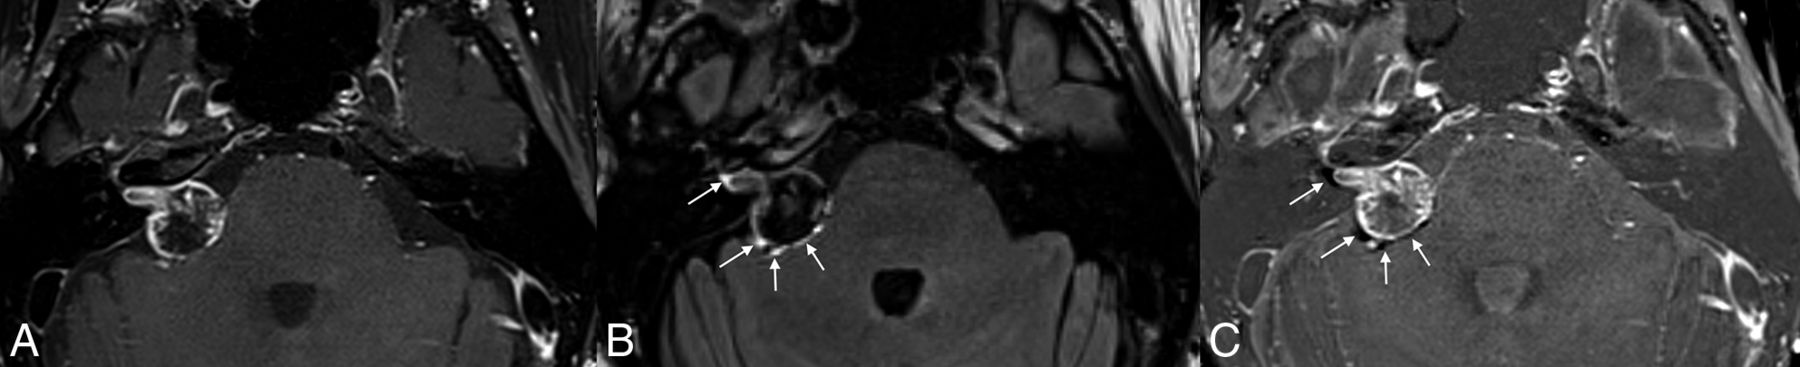

Hyperintense peritumoral signal (halo) was present on postcontrast FLAIR images in 90% of patients. In general, the observed halo was nonuniform in thickness around the circumference of the tumors (Fig 1). The halo itself was difficult to confirm as being outside the tumor borders without the use of overlay/fused images in the PACS system. The average maximum thickness of the halo in the axial plane was 1.0 (SD, 0.2) mm. Interobserver agreement regarding the presence or absence of a halo was nearly perfect (κ = 0.95), while the interobserver correlation coefficient of the halo thickness was 0.38.

Example of a peritumoral halo on postcontrast FLAIR images. Postcontrast fat-saturated T1-weighted image (A) demonstrates a vestibular schwannoma extending from the right IAC into the CPA. Postcontrast FLAIR image (B) shows a discontinuous peritumoral hyperintense halo that extends beyond the tumor margins on postcontrast T1-weighted images (arrows). Corresponding subtraction FLAIR image (C) confirms the presence of a halo (arrows).

Regarding the 2 tumors that lacked a halo, one was 14 mm and the other was 8 mm. The 14-mm tumor lacked a fundal cleft, potentially affecting the ability to visualize a peritumoral halo. Both fusion and subtraction on the 8-mm tumor were somewhat difficult, possibly affecting the ability to visualize a halo in that lesion.